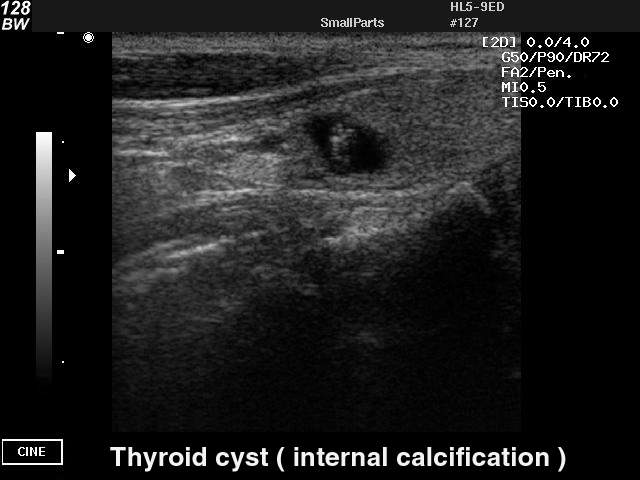

Киста щитовидной железы

Киста щитовидной железы на УЗИ